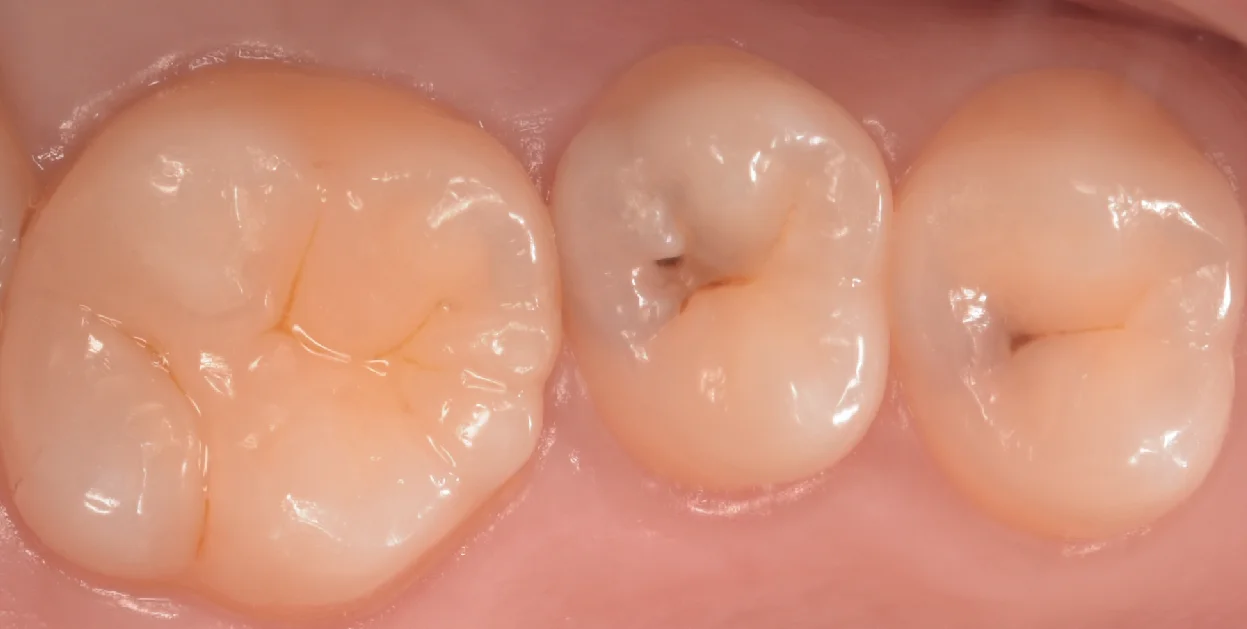

まずは術前からです。

画像上で右二つの治療を今回行いました。

ちなみに左の大きな歯についてはこの1ヶ月程前に治療を行ったものになります。

なんとなく歯の内部が黒っぽいのがわかりますかね?